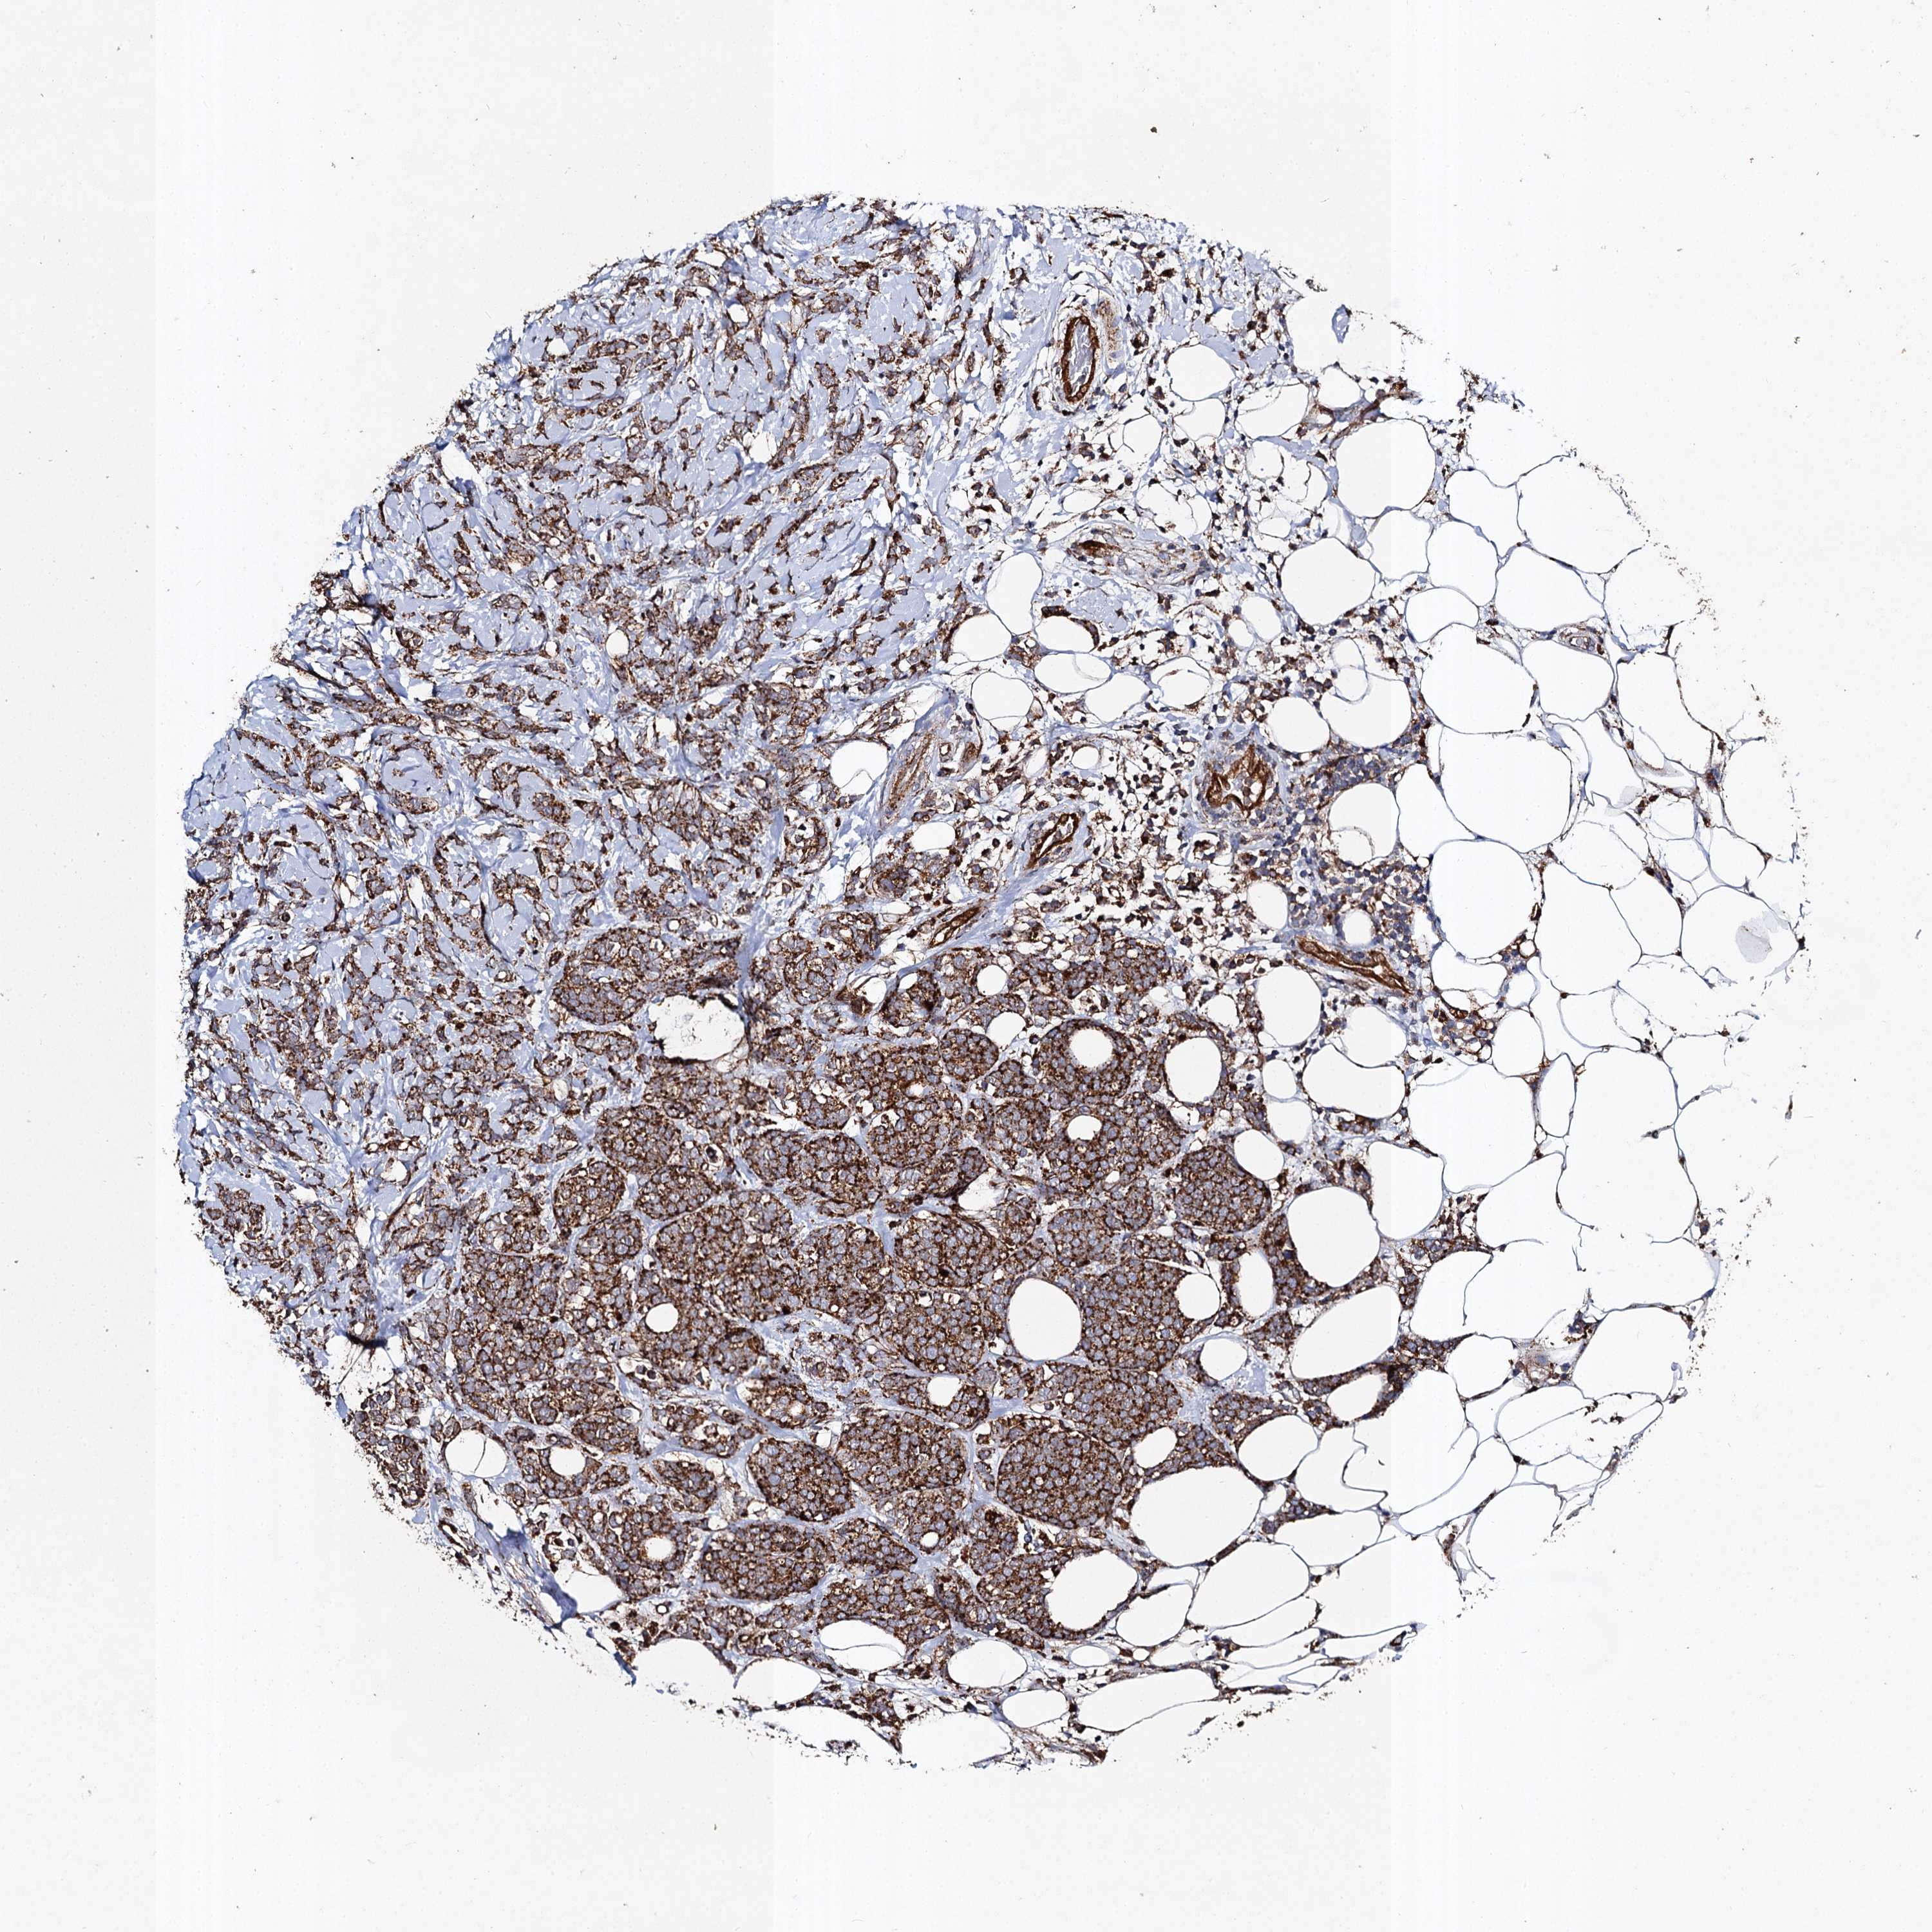

CANCER BREAST CANCER Show tissue menu

BRCA TCGA BRCA VALIDATION PROTEIN EXPRESSION

Breast cancer

Human cancer

Breast invasive carcinoma